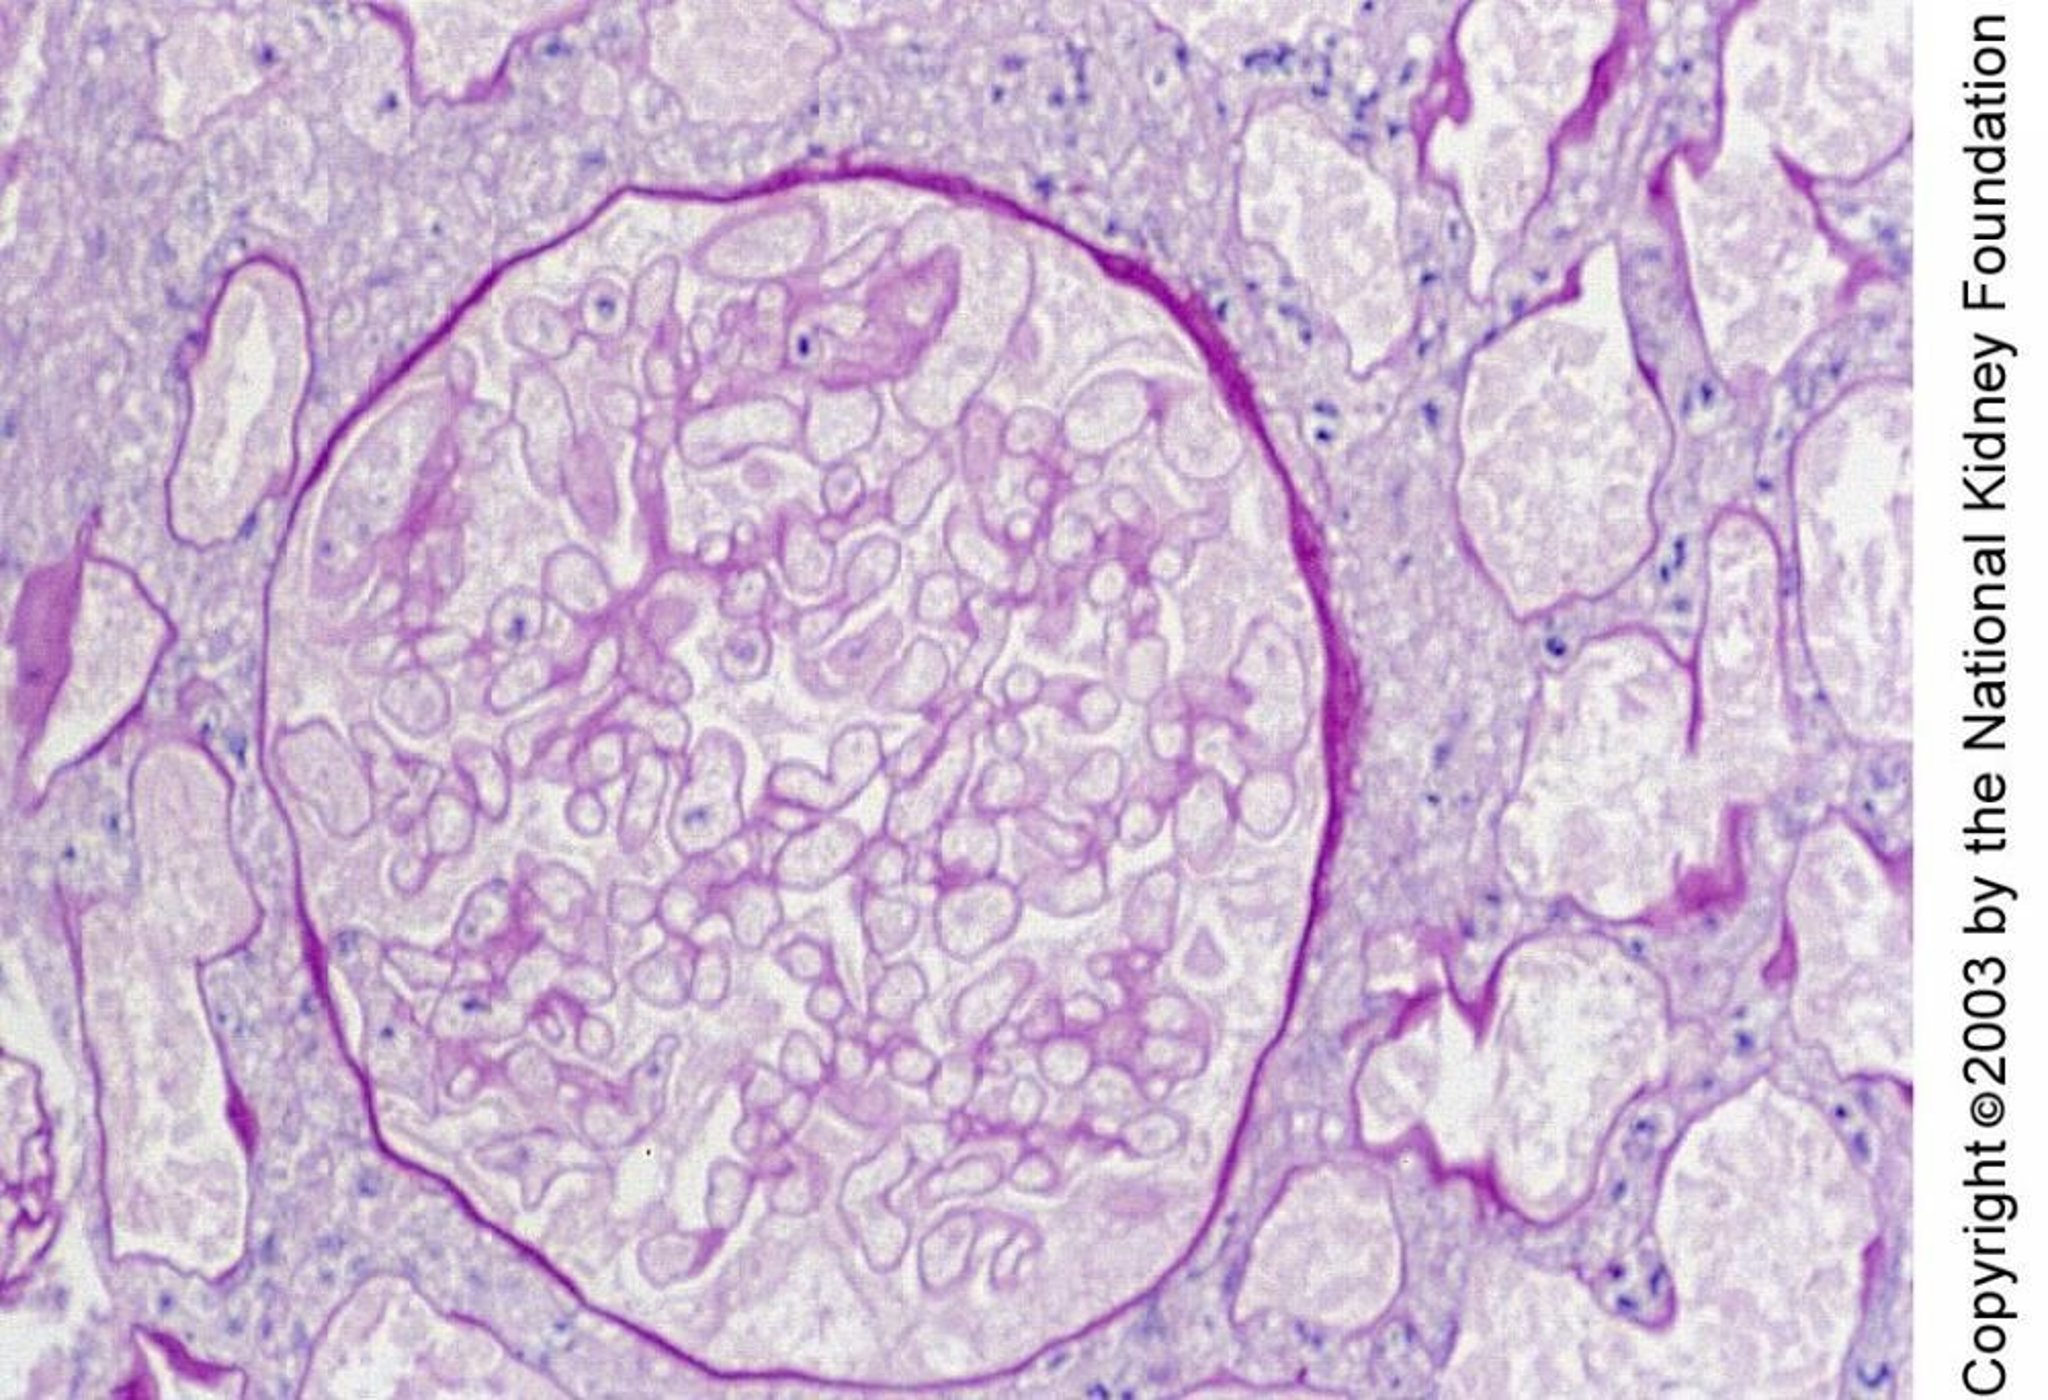

Nécrose corticale rénale

La nécrose corticale rénale est caractérisée histologiquement par la nécrose des glomérules et des tubules. La nécrose sur ce prélèvement de biopsie se manifeste par de petits noyaux et des contours de cellules fantômes (coloration à l'acide périodique Schiff, × 400).

Image fournie par Agnes Fogo, MD, and the American Journal of Kidney Diseases' Atlas of Renal Pathology (voir www.ajkd.org).